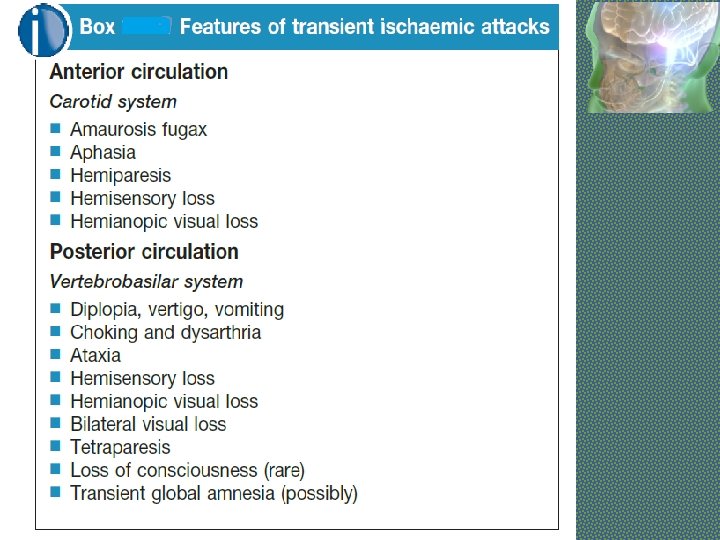

Types of Stroke Depending upon the rate of developing and reversibility, stroke can be of following types: § Transient Ischemic Attack (TIA): means a brief episode of neurological dysfunction due to temporary focal cerebral or retinal ischemia without infarction, e. g. a weak limb, aphasia or loss of vision, usually lasting seconds or minutes with complete recovery. § Stroke-in-Evolution: If neurological deficit increases by step wise progression or there is slow uninterrupted progression, it is called stroke-in-evolution. It may take 12 weeks to complete § Complete Stroke: It means complete hemiplegia § RIND (Reversible Ischemic Neurological Deficit): It is a term that is not widely used anymore. It means a stroke that the patient was able to fully recover from within a few weeks.

Types of Stroke Depending upon the blood supply of affected area of brain, stroke can be of following types: § ANTERIOR CIRCULATION STROKE: Carotid system § POSTERIOR CIRCULATION STROKE: Vertebrobasilar system

Amaurosis fugax • Refers to a transient loss of vision in one or both eyes due to embolism in retinal artery. • This is a feature of TIA in carotid circulation

ISCHEMIC STROKE Cerebral Thrombosis: § § § Occurs when patient is asleep Atherosclerotic narrowing of blood vessel Middle cerebral art is commonly involved Patient usually remain conscious HTN is a major risk factor Clinical Features: ØPt can not move one half of body ØDysphasia ØUncrossed hemiplegia ØHigh BP ØCarotid Bruit

ISCHEMIC STROKE Cerebral Embolism: § Sudden onset § Past history of TIAs § Source of Embolism q Carotid artery atheroma (weak carotid pulse, bruit) q Atrial Fibrillation or other arrythmias q Recent Myocardial Infarction q Valvular Heart Disease q Infective Endocarditis § Clinical Features: Ø Sudden loss of power in one half of body Ø Conciouness may be lost Ø Dysphasia Ø Uncrossed hemiplegia Ø Irregular Pulse Ø Signs of valvular heart disease Ø Carotid Bruit

MIDDLE CEREBRAL ARTERY • Supplies lateral surface of frontal, perital and temporal lobes • Most of the motor and sensory cortex Ecxept the part on medial side and control lower limb, internal capsule Total Occlusion: • Uncrossed hemiplegia • Hemianesthesia • Global Dysphasia • Homonymous hemianopia • Apraxia, Agnosia Partial occlusion: • Any of the above features. • Lower limb is either not or minimally involved

ANTERIOR CEREBRAL ARTERY • Supplies MEDIAL surface of hemisphere • Motor and sensory cortex on medial side which control lower limb • Soon its origin it gives a penetrating branch (Heubner’s artery) which supply internal capsule (containing fibers of upper limb and face) Occlusion at the origin: Features are similar to total occlusion of MCB Occlusion of Heubner’s artery : • Weakness of upper limb and face Occlusion after the origin of Heubner’s artery : • Weakness of lower limb • Loss of cortical sensory function in lower limb

POSTERIOR CEREBRAL ARTERY • Branch of Basilar artery • Supplies occipital lobe which include visual cortex Occlusion: • • Visual field loss Homonymous hemianopia Visual agnosia Disorders of reading Disorders of color vision Memory impairment Motor dysfunction